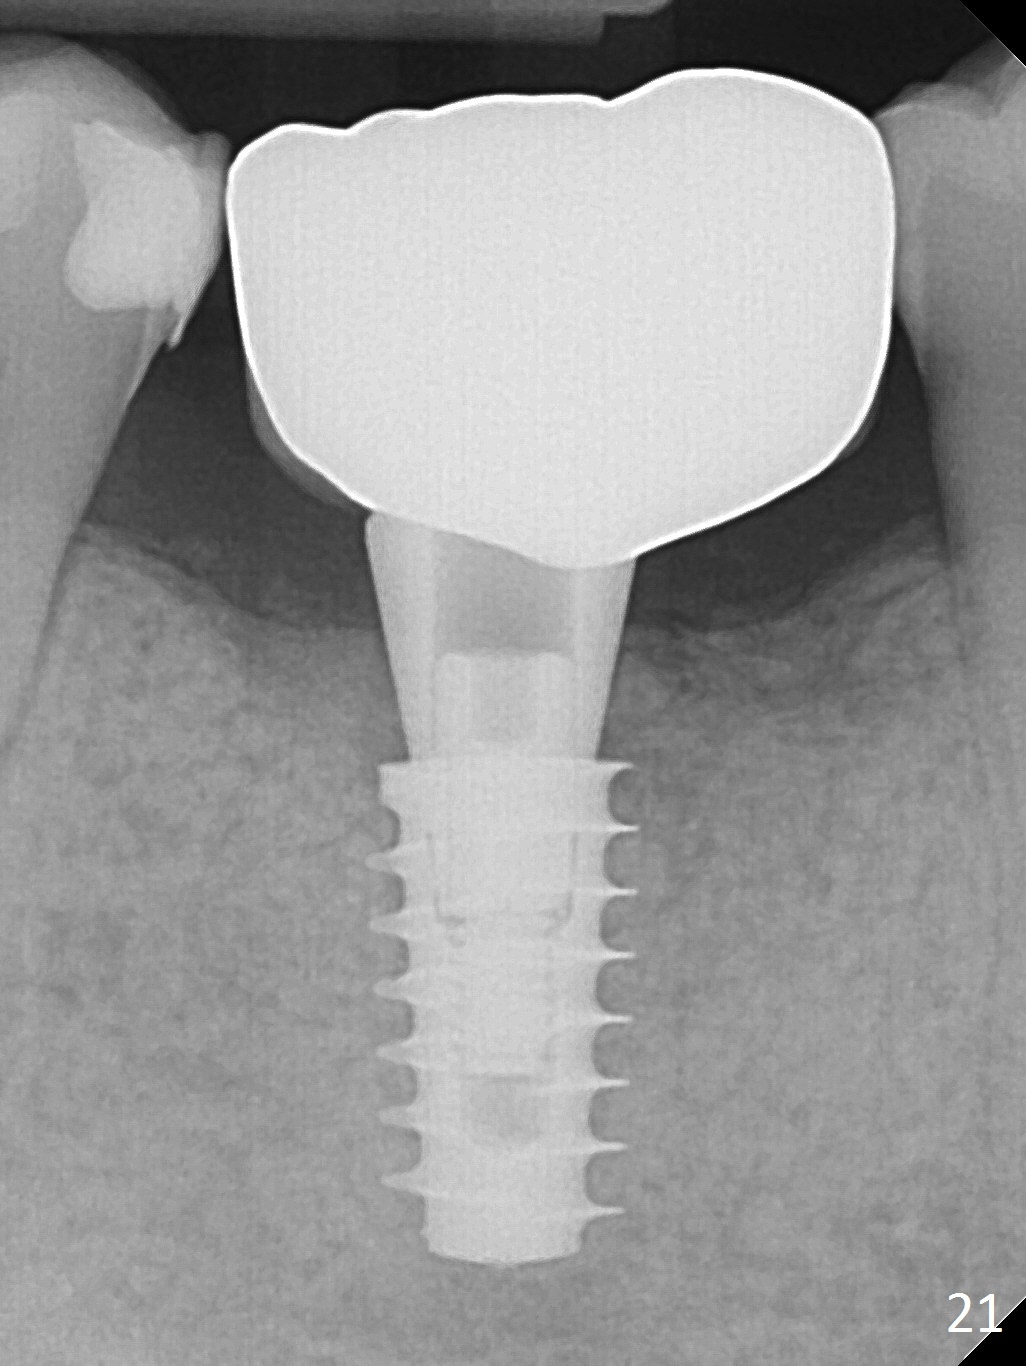

Three weeks later (5.5 months postop), a permanent crown tries in with healthy keratinized gingiva (Fig.18). The provisional keeps normal gingival bed (Fig.19), while the abutment forms tissue cuff (Fig.20). After cementation, PA shows bone regeneration (Fig.21). The gingiva remains healthy 8.5 months post cementation (Fig.22). Bone density around the implant increases 1 year 2 months post cementation (Fig.24). The gingiva remains healthy 2 years 4 months post cementation (Fig.25).